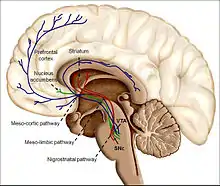

The substantia nigra is a small midbrain area that forms a component of the basal ganglia. This has two parts—an input area called the pars compacta and an output area the pars reticulata. The dopaminergic neurons are found mainly in the pars compacta (cell group A8) and nearby (group A9).[42] In humans, the projection of dopaminergic neurons from the substantia nigra pars compacta to the dorsal striatum, termed the nigrostriatal pathway, plays a significant role in the control of motor function and in learning new motor skills.[44] These neurons are especially vulnerable to damage, and when a large number of them die, the result is a parkinsonian syndrome.[45]

The ventral tegmental area (VTA) is another midbrain area. The most prominent group of VTA dopaminergic neurons projects to the prefrontal cortex via the mesocortical pathway and another smaller group projects to the nucleus accumbens via the mesolimbic pathway. Together, these two pathways are collectively termed the mesocorticolimbic projection.[42][44] The VTA also sends dopaminergic projections to the amygdala, cingulate gyrus, hippocampus, and olfactory bulb.[42][44] Mesocorticolimbic neurons play a central role in reward and other aspects of motivation.[44] Accumulating literature shows that dopamine also plays a crucial role in aversive learning through its effects on a number of brain regions.[46][47][48]

The largest and most important sources of dopamine in the vertebrate brain are the substantia nigra and ventral tegmental area.[42] Both structures are components of the midbrain, closely related to each other and functionally similar in many respects.[42] The largest component of the basal ganglia is the striatum.[52] The substantia nigra sends a dopaminergic projection to the dorsal striatum, while the ventral tegmental area sends a similar type of dopaminergic projection to the ventral striatum.[42]